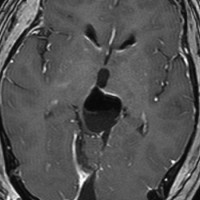

tectal gliomaに間違えそうなPPTID 松果体実質腫瘍

上段のガドリニウム増強MRIでは松果体腫瘍に見えやや境界が不明瞭なので,年齢からはPPTIDが疑われます。しかし,CISSの画像で,中脳上丘との境界がなく中脳腫大があるようにみえ,テクタールグリオーマを疑って経過観察しました。腫瘍がゆっくり増大したので摘出したところPPTIDという診断がつきました。